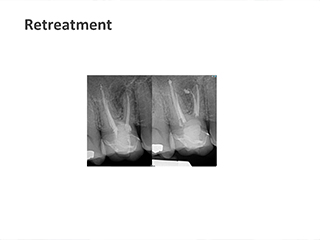

We take pride in providing the highest standard of care at ICE and believe that only the best is good enough for our patients. As such, Shakil completes all endodontic procedures using a state-of-the-art dental microscope. We accept referrals for consultations, root canal treatment (primary and retreatment), management of endodontic emergencies, dentoalveolar trauma and we are also happy to provide definitive restorations as required.